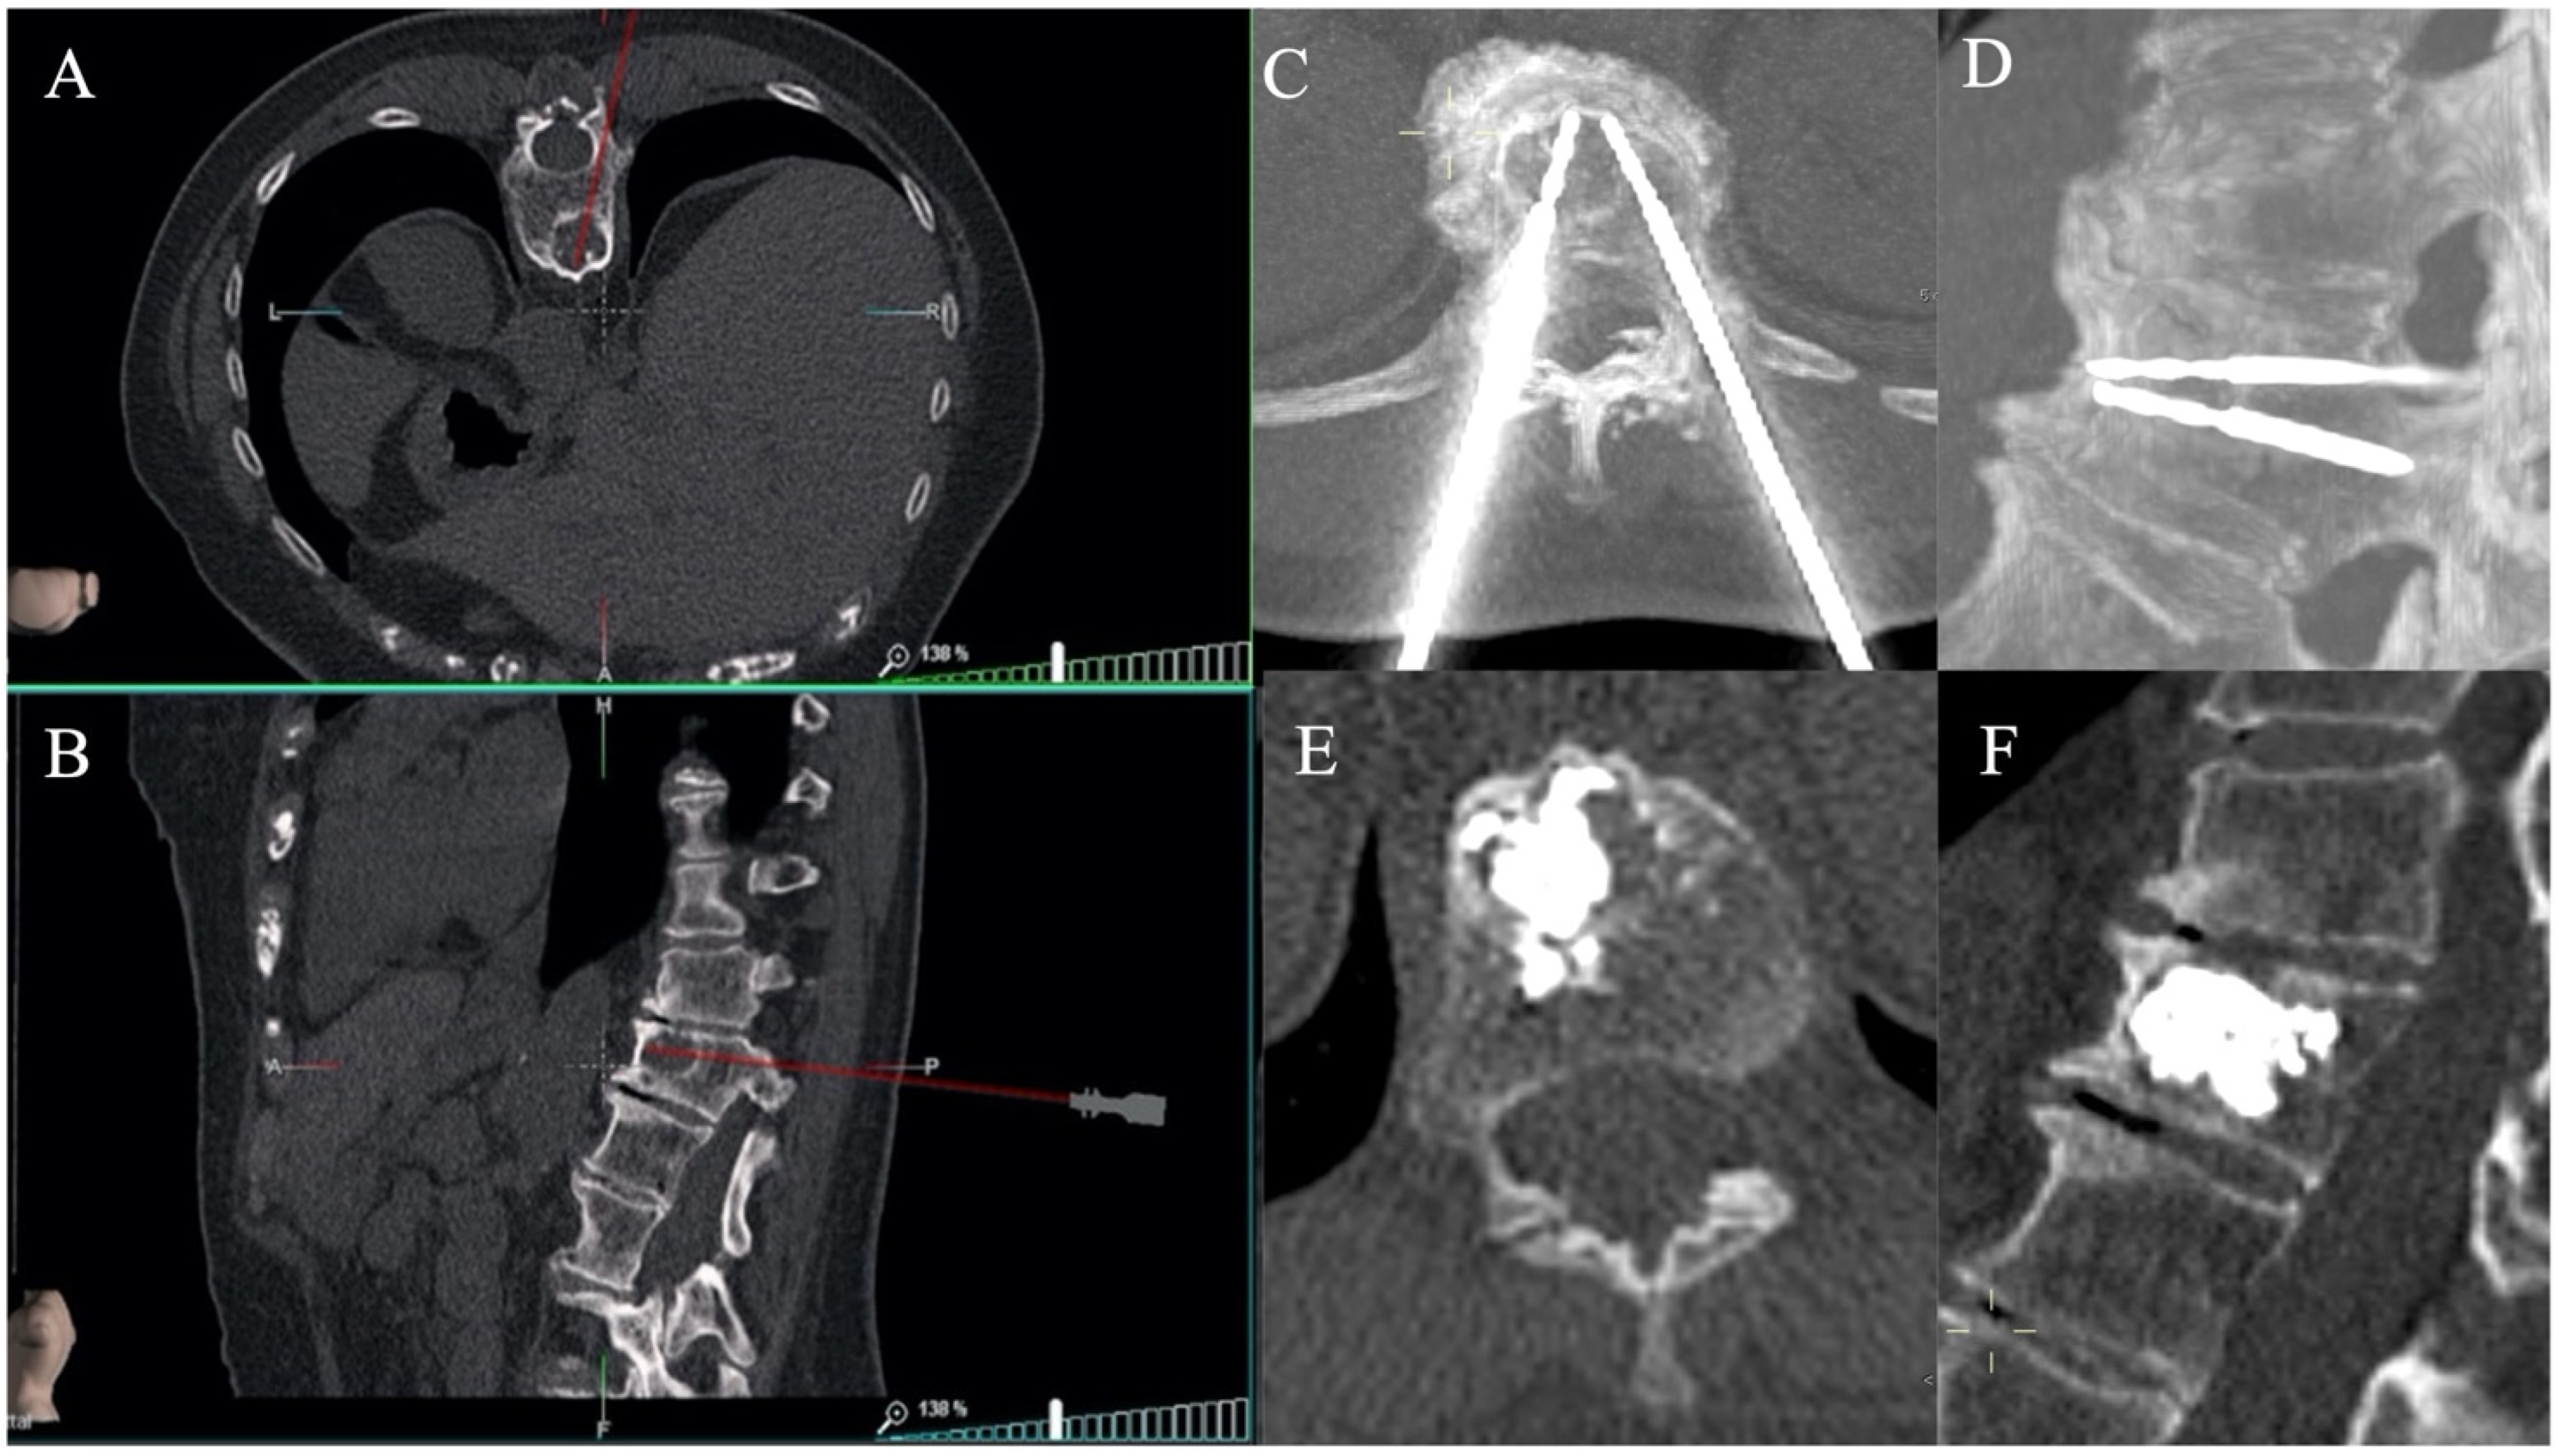

Figure 4.

F: 68yo with a lumbar vertebral body metastasis from breast cancer. Needle positioning was performed with the aid of CT and an optical-based navigation system (SIRIO, MASMEC S.p.A., Modugno, Bari, Italy), to perform an ablation procedure followed by vertebroplasty. Axial (A) and sagittal (B) reconstructions of the virtual 3D CT model showing needle trajectory; axial (C) and sagittal (D) reconstruction CT images confirming the correct positioning of the needles within the lesion; axial (E) and sagittal (F) CT reconstructions demonstrating optimal final cement distribution within the vertebral body.